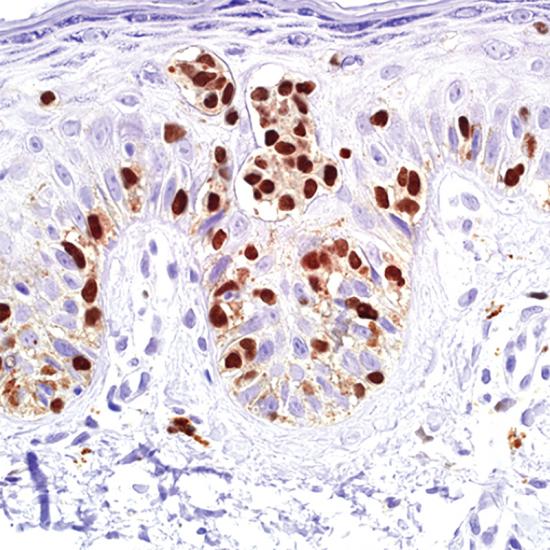

小眼相關(guān)轉(zhuǎn)錄因子(MiTF)抗體試劑(免疫組織化學(xué)法) 閩廈械備20190170號

細(xì)胞核

黑色素瘤

MiTF是一種黑色素核標(biāo)記物。研究表明,這是一個(gè)敏感、特異的惡性黑色素瘤的標(biāo)記物。MiTF已被證明其特異性和敏感性比S100和HMB45更高。MiTF可以用識別黑色素瘤。